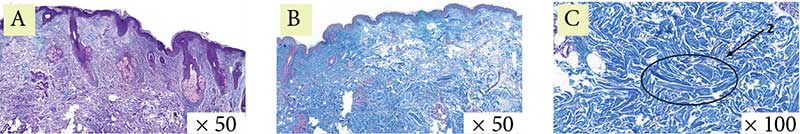

Рис. 3. Пациентка 1. Окраска по Массону: A – до процедуры, B и C – через месяц после процедуры (стрелка указывает на участок упорядочения и структуризации коллагеновых волокон)

Гистологическая картина демонстрирует уменьшение гиперкератоза, сглаживание эпидермальных гребней. В сосочковом слое дермы отмечаются компактизация и реорганизация коллагеновых волокон, в сетчатом слое дермы коллагеновые волокна стали более структурированными и упорядоченными (рис. 7–9).